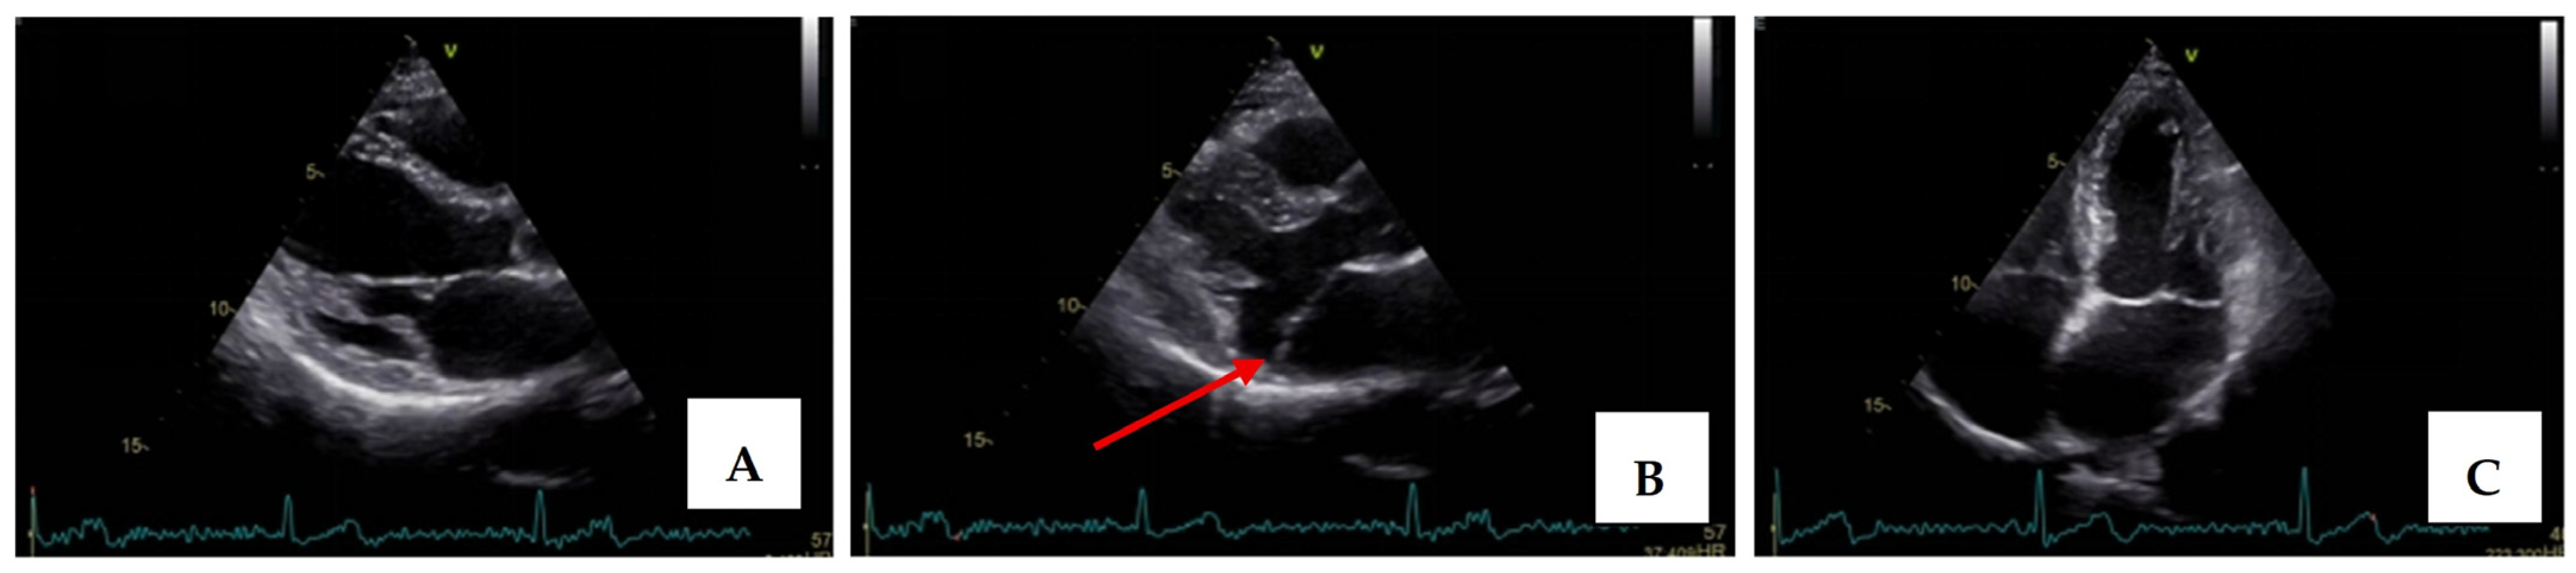

Transthoracic echocardiography revealed myxomatous degeneration of the mitral valve with bileaflet redundancy, increased leaflet length and thickness, and prolapse of both leaflets. Notably, a mitral annular disjunction (MAD) measuring 10 mm was observed in the parasternal long-axis view at end-systole (Figure 2A–C). Additionally, systolic “curling motion” of the posterolateral wall of the left ventricle was present, and the Pickelhaube sign was documented (Figure 3).

Mitral valve prolapse with MAD on transthoracic echocardiography (TTE). (A)—TTE parasternal long-axis view in end-diastole displaying excessive leaflet length and thickness, (B)—TTE parasternal long-axis view in end-systole displaying mitral annular disjunction-MAD of 10 mm length (red arrow), and (C)—apical 4-chamber view displaying a displacement of both leaflets > 2 mm above the plane of the annulus.

Severe mitral regurgitation was identified, manifested by an eccentric regurgitant jet and associated left atrial dilatation (Figure 4). Moderate tricuspid regurgitation with right atrial dilatation was also present. Both the left and right ventricles were of normal size and function. Global longitudinal strain was preserved for both ventricles, with an average of −22.9% for the left ventricle and −22.0% for the right ventricle, although a mild degree of dispersion in longitudinal strain peaks was observed (Figure 5).

Apical four chamber view showing severe mitral regurgitation with left atrial dilatation.